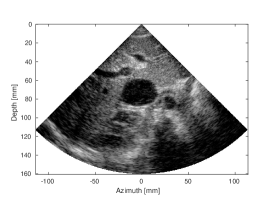

| (a) SLT | (b) MLT, (Tukey, =0.5) | (c) MLT, CNN | |

| CNR=2.33, CR=-29.33dB | CNR=1.69, CR=-19.16dB | CNR=2.2, CR= -29.24dB | |